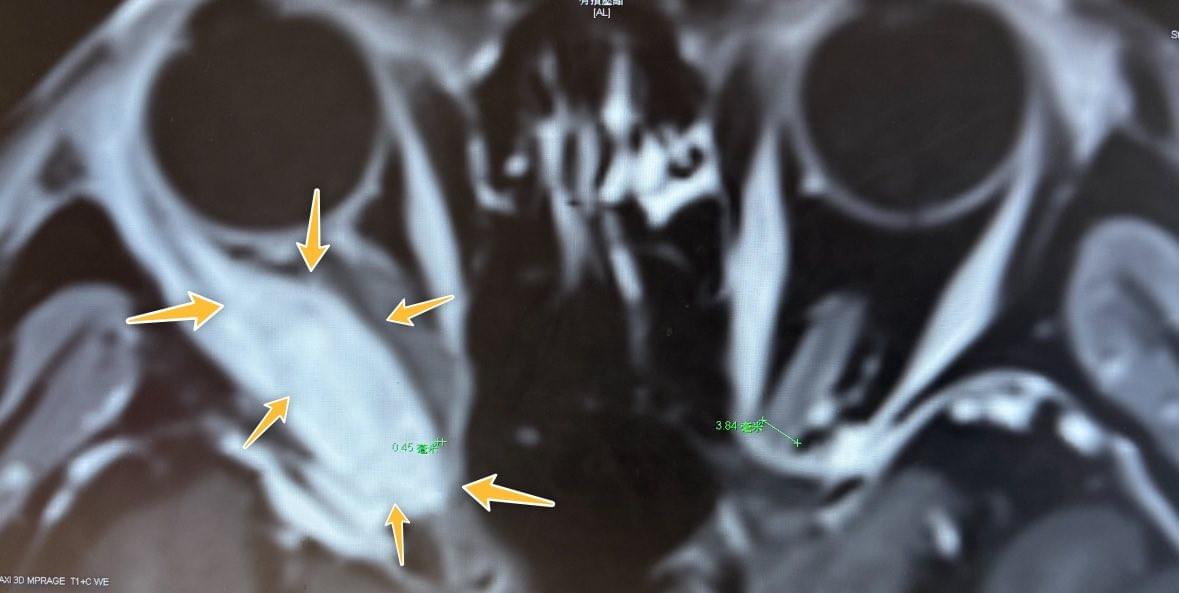

約五十歲中年女性,近一年發生右眼眼凸狀況,右眼視力與眼動也有影響。後期還有複視問題。經外院詳細影像檢查後,發現一個眼眶內強烈顯影病灶。這個病灶壓迫到眼球,也壓迫到右側視神經。

回到這位病患,她來住院時大概不知道外科醫師內心深處那個磨刀霍霍的眼神。雖然只是診斷性的切片手術,但還是有時候你的經驗、知識與聯想力還是會幫助你在術前推測診斷。我術前的影像臆斷原本是眼內淋巴瘤。眼內淋巴瘤佔中樞系統淋巴瘤約3%,超級罕見。不過我還注意到一件事,病患近一年體重掉了兩公斤,睡眠時間減少。

術前的荷爾蒙檢查被我抓到甲狀腺功能亢進。這件意料之外的事大大在我心中亮起紅燈。以前讀書時我知道甲狀腺Graves disease 會造成眼眶內結構改變,主要是眼外肌與脂肪體積增加,造成凸眼症。不過我查了一下文獻好像沒有明確的文獻說明這樣的結構變化會改變顯影訊號。

迫不得已,我暫停了手術計劃,找了本院兩位內科大名鼎鼎的王牌醫師來討論:血腫科神醫王大大與新代科康健良醫周主任。這個團隊討論雖然沒有明確的結論,但王大大的意見讓我覺得這個病患不像眼內淋巴瘤。而且後續病患的甲狀腺亢進經周主任的檢查確認是Grave Disease(葛瑞夫茲病),一種甲狀腺自體免疫性疾病。於是我宣布暫不手術,先把病患轉給周主任治療甲狀腺疾病。病患就出院了。

經過內科治療,一個月後病患的眼內病灶真的就明顯消減,顯影訊號也減弱。三個月後這個病灶就消失了。病患所有的理學症狀及神經學症狀都完全康復了。